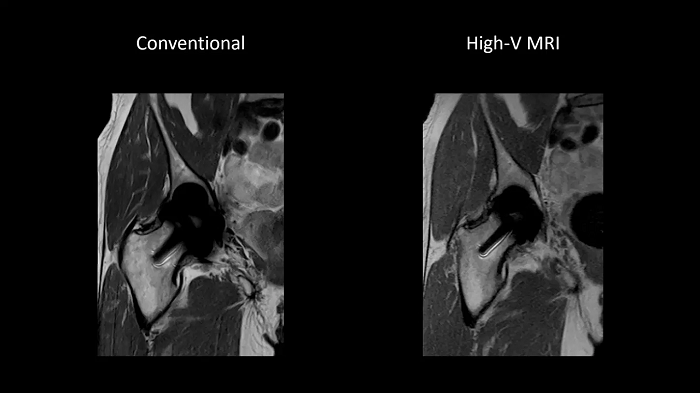

Improved implant imaging with High-V MRI

The imaging of metal implants has historically been difficult with conventional MRI systems as metal causes artifacts. High-V MRI offers intrinsic physical advantages that result in reduced metal distortions and strongly improved diagnostic capabilities for implant imaging.

Image Courtesy: University Hospital Erlangen, Germany | Image-ID: 1aaaa3623 | 4aaaa0399